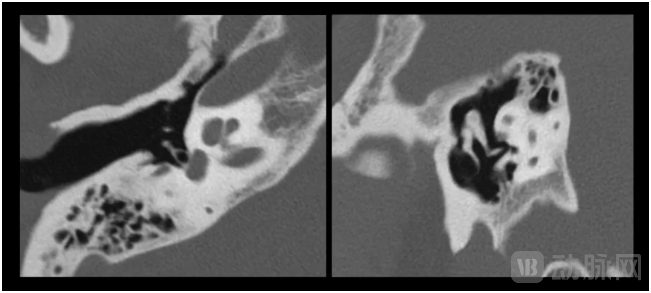

东软医疗公布的部分影像数据就显示,NeuViz 1024能够清晰显示耳、口腔、骨小梁等细微的身体结构,进而为更深层次的精准诊疗、科研探索提供新的工具支撑。

NeuViz 1024内耳听小骨成像